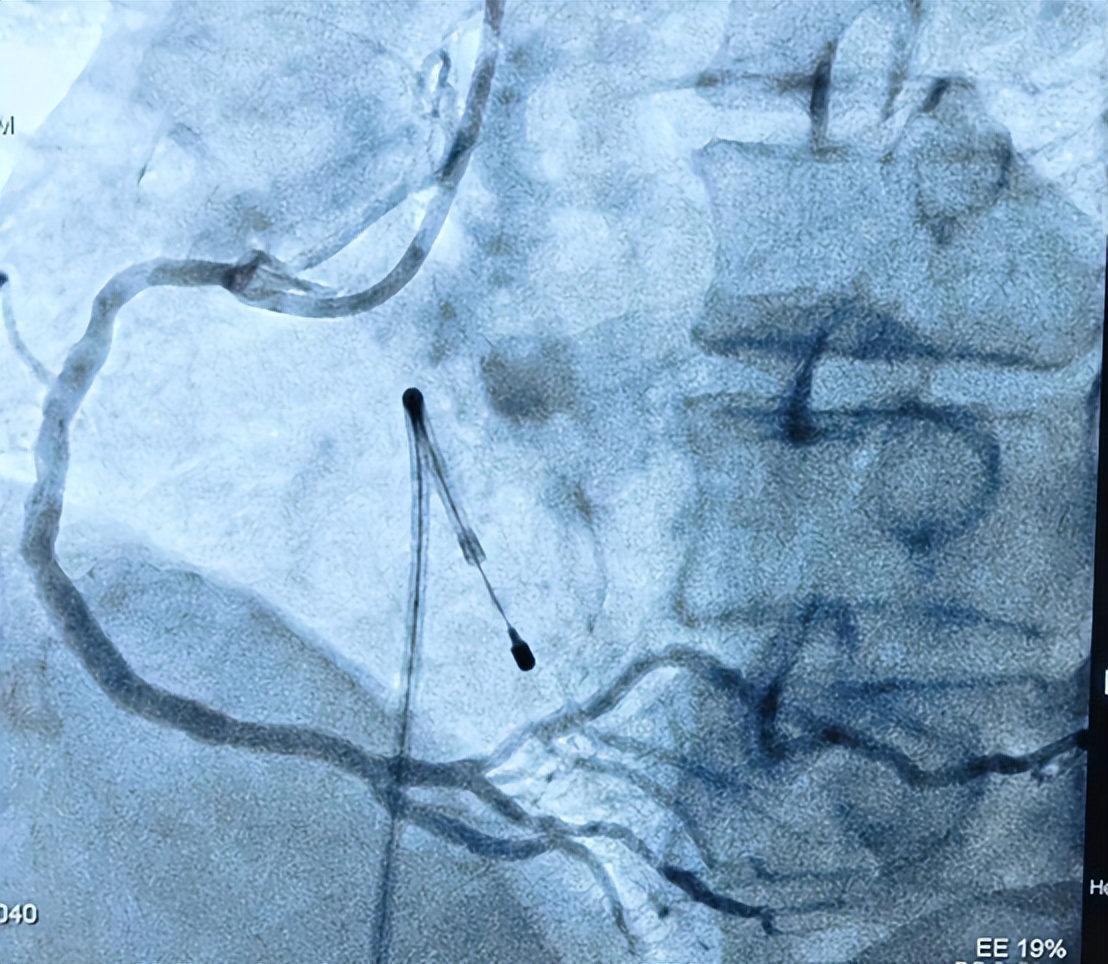

第1个是李臻医生在上班期间收治的胸口难受病人,做了心电图发现可能急性心肌梗死了,不等血清标志物结果,秉着“时间就是心肌”的原则,立即启动了急诊介入程序,很快时间我和他配合完成了冠脉造影,发现回旋支近段闭塞,考虑为本次罪犯血管,请示上级医师后立即行PCI术处理回旋支闭塞病变,术中在导丝通过闭塞病变后,病人血压逐渐下降,心电监护提示频发早搏,考虑为再灌注心律失常,立即予静滴去甲肾上腺素升压,静推胺碘酮控制心室率过渡,在梗死心肌再灌注一段时间后,患者生命体征逐渐平稳,血压回升,早搏消失,心率稳定;然后继续手术,对闭塞病变进行扩张后复查造影发现回旋支远段也有重度狭窄,最终成功在回旋支远段靶病变使用1枚药物球囊,近段闭塞病变处植入1枚支架,术后患者症状完全消失,生命体征平稳。

回旋支近段闭塞

术后回旋支完全的血运重建